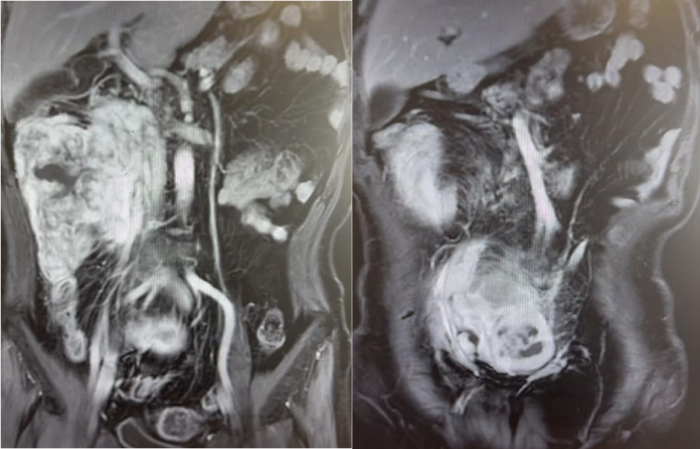

56岁男性患者,因间断上腹不适4个月,检查发现腹膜后肿瘤2周。腹部CT及核磁提示腹膜后巨大脂肪肉瘤,直径约35cm。

我们为患者实施全麻下开放腹膜后肿瘤切除术。术中可见肿瘤挤压十二指肠、胰头、肠系膜血管、下腔静脉和腹主动脉,但未侵犯结肠、肠系膜血管等组织器官,且包膜完整。手术团队仔细游离,完整切除腹膜后肿瘤,剔除腹膜后脂肪。历时2个小时完成,术中出血约100ml。

术后恢复顺利:第3天排气并进食流食;第5天恢复正常饮食;术后第9天出院。术后病理高分化脂肪肉瘤,肿瘤最大径38cm,与肾周脂肪粘连。术后3月随访,未见肿瘤复发。